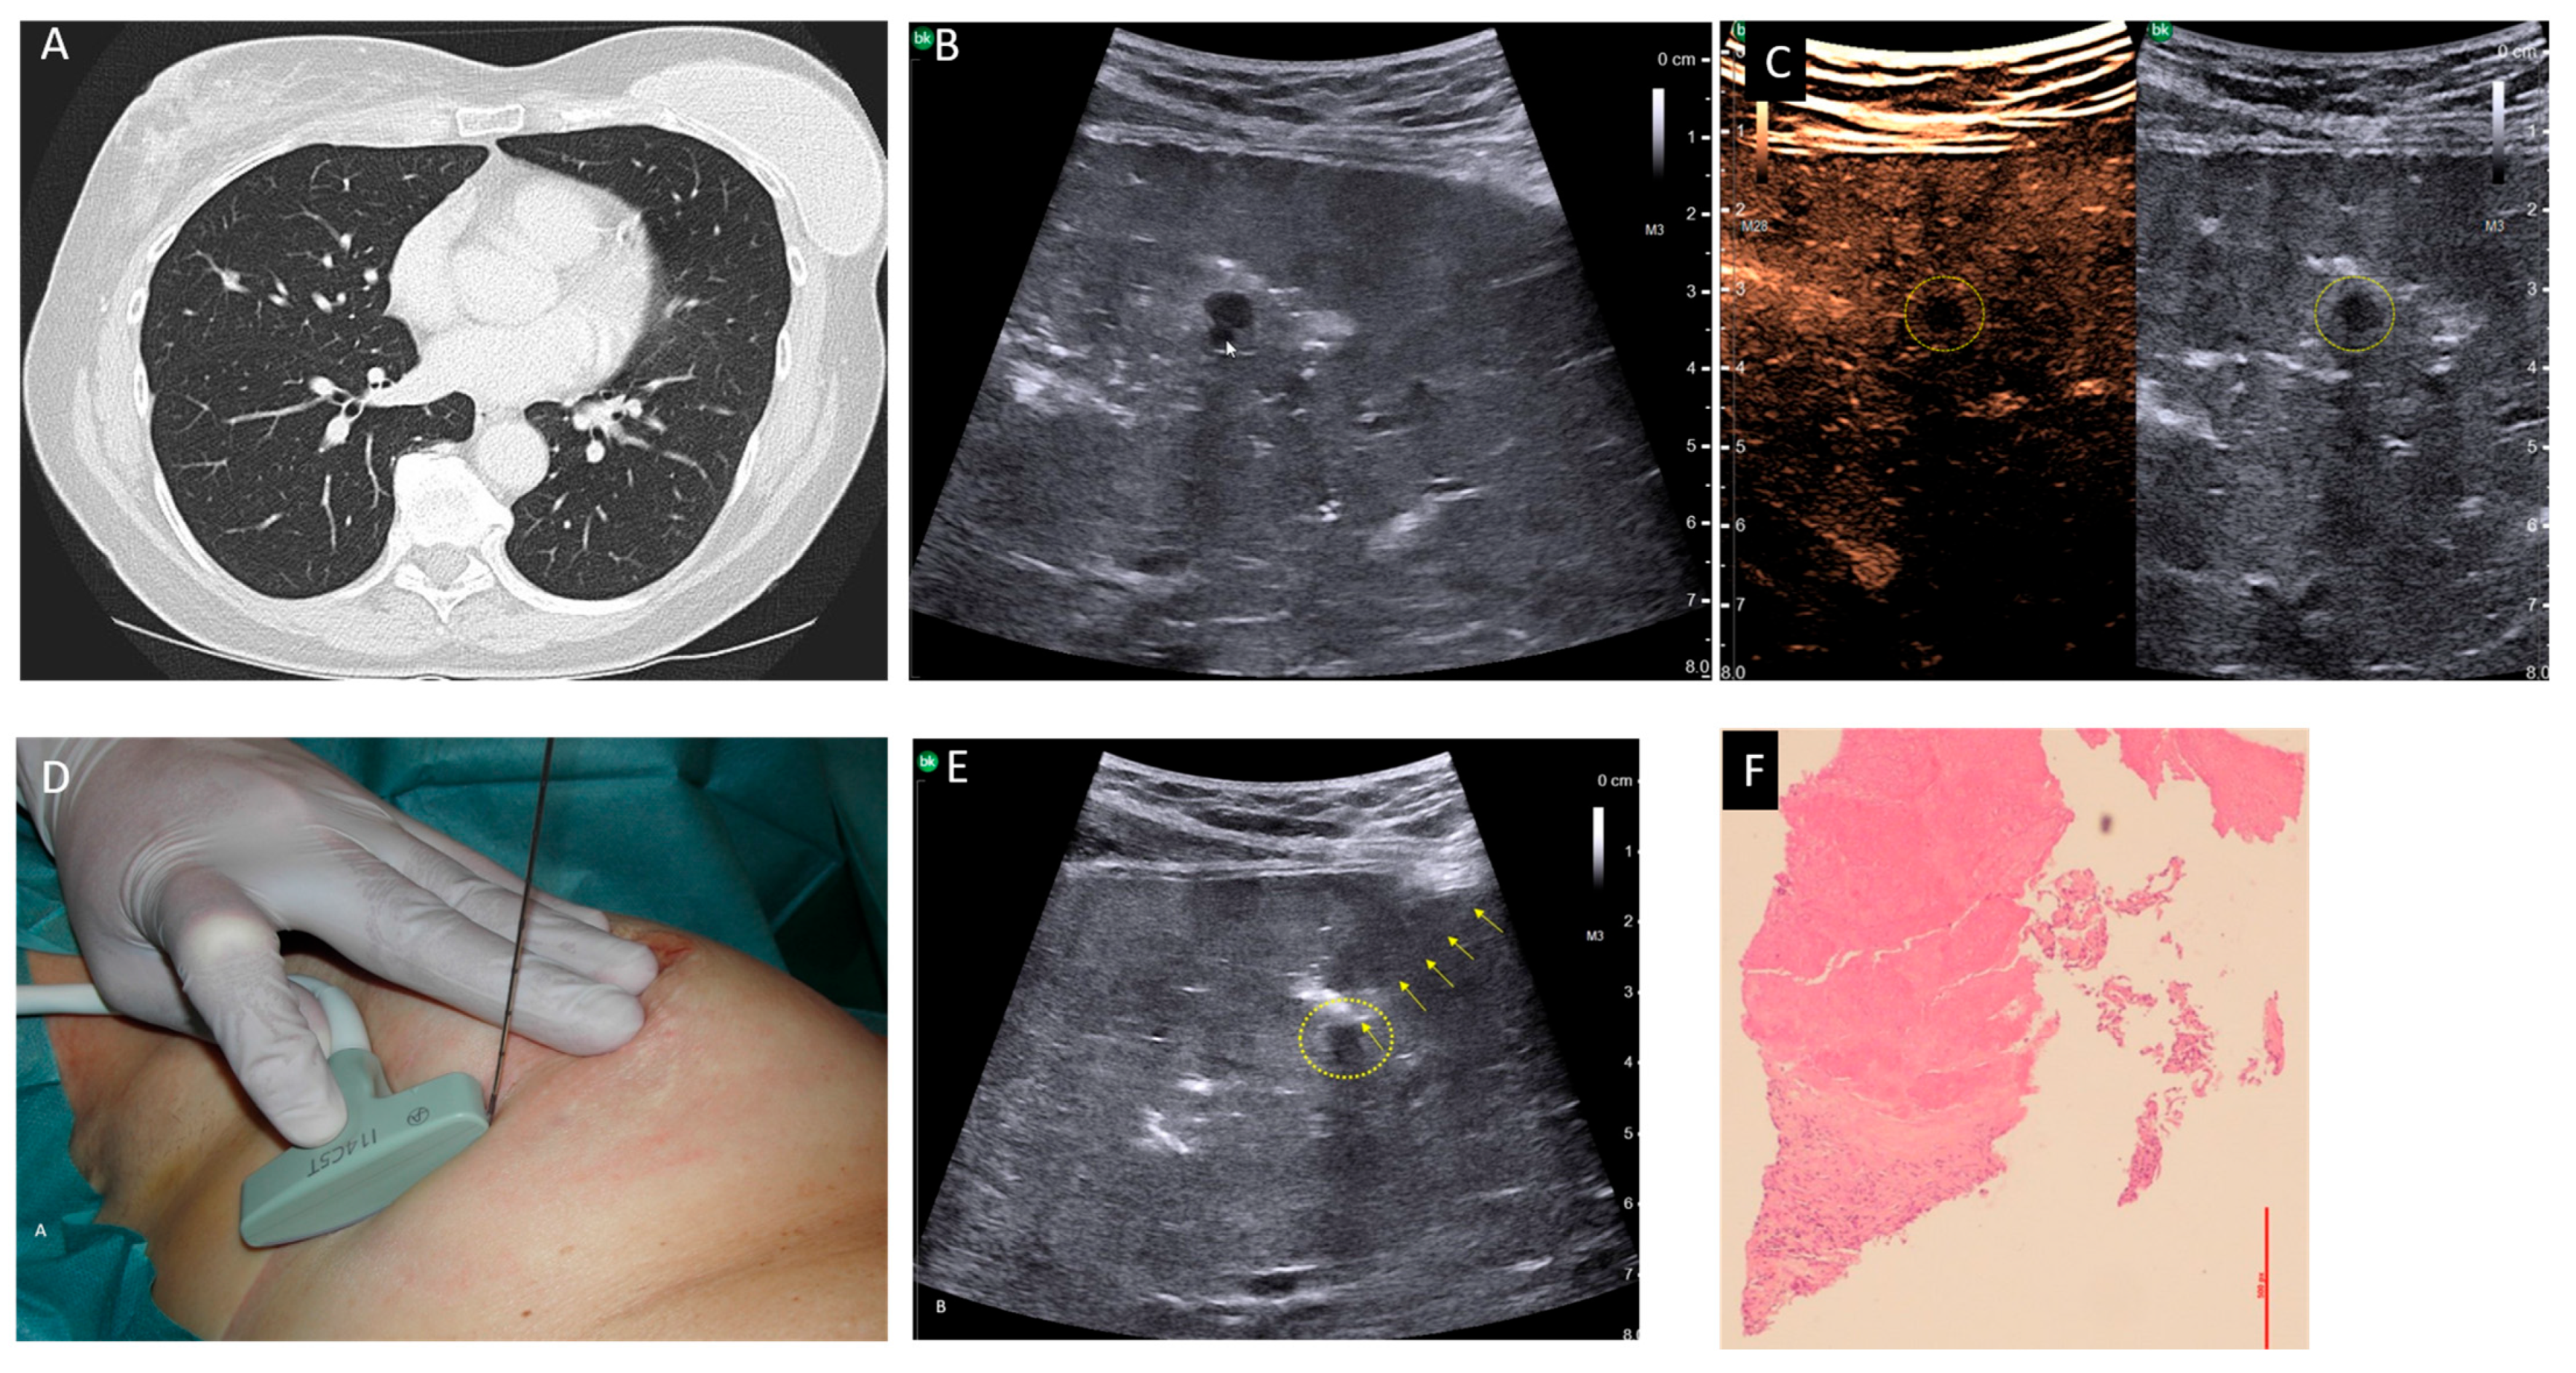

Our second case was a 61-year-old patient suffering from a breast carcinoma on the right side. Twelve years ago, she received an operation and radio-chemotherapy due to a breast carcinoma on the left side. During staging, a chest CT-scan demonstrated a small pulmonary nodule about 5 mm in size in the middle lobe, which was new compared with a follow-up CT 6 months ago and suspected to be metastasis (Figure 1A). A histological confirmation was necessary for staging and to determine the therapeutic strategy. To avoid a thoracotomy, the patient was suggested a USgTTcNB under OLF. As described above, the right lung was filled with saline. A smoothly marginated hypoechoic nodule about 5 mm in size, which was directly adjacent to a vessel, was located 3 cm below the pleura (Figure 1B). Contrast-enhanced ultrasound revealed no perfusion into the nodule (Figure 1C). A USgTTcNB (18G, BARD®MAX-CORE®; BARD GmbH Karlsruhe, Germany) under OLF was performed (Figure 1D). The results from the frozen section procedure showed complete necrosis, confirmed after formalin fixation (Figure 1E). Since malignancy was extremely unlikely due to the 1 mm thick, 7 mm long core biopsy and no contrast enhancement occurred during ultrasound, the patient was extubated. Two hours later, a small apical pneumothorax was diagnosed via ultrasound and X-ray, and then evacuated using a thin (8F) pleural catheter, which could be removed after four hours. The further course of treatment was uncomplicated with normal blood gas analysis. Ultrasound and X-ray follow-ups on the second and ninth postoperative days showed no evidence of pleural effusion, pneumothorax, or residual fluid in the lungs (Supplementary Figure S3). Body plethysmography on the second postinterventional day showed an increase in diffusing capacity and a decrease in residual volume and functional residual capacity compared with pre-intervention values (Figure 2). The patient was thus discharged on the third post-interventional day.

Figure 1. (A) CT scan showing a small pulmonary nodule adjacent to a vessel within the middle lobe. (B) Transthoracic ultrasound of the right lung under OLF revealing a smoothly marginated hypoechoic nodule adjacent to a vessel (arrow). (C) Contrast-enhanced ultrasound of the flooded lung showing a hypoechoic nodule (dashed circle) without contrast enhancement. (D) Free-hand ultrasound-guided biopsy using a T-shaped intraoperative transducer (bK medical GmbH, Quickborn, Germany). (E) Transthoracic lung ultrasound under OLF with a core biopsy needle (arrows) inserted into the nodule (dashed circle). (F) Histological image of the core biopsy showing a complete necrotic area above and vital normal lung tissue below (hematoxylin–eosin stain).